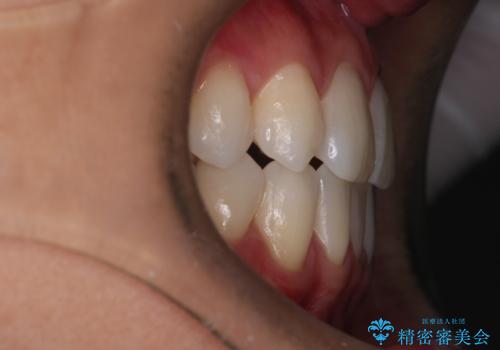

右上2番が欠損しているため、見た目と噛み合わせの両方のバランスを整えるために経過を追いながら必要な部位にゴム掛けをしました。

最終的に、見た目も噛み合わせも患者様に満足いただけました。